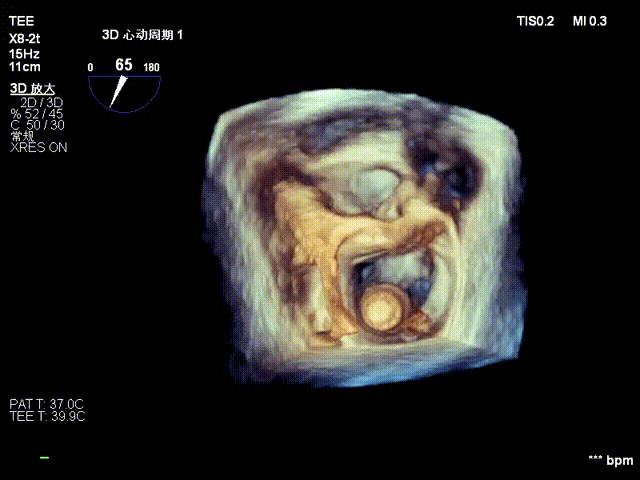

术前心超提示:

退行性二尖瓣反流(DMR),A2-A3脱垂伴连枷样运动(脱垂范围:17mm,连枷间距:7mm),P3脱垂,反流主要位于2-3区,MR重度4+(VC:6*17 mm),A3:18mm,P3:9mm,A2:24mm,P2:14mm,AP:32mm,二尖瓣口面积MVA约 5.6cm²,左房、左室明显扩大。

术中操作(关键步骤超声)

在全麻下,于心尖入路完成ValveClamp®装置植入。术中多学科团队密切配合,超声全程实时指导操作。最终,于2偏3区成功植入一枚Ⅲf夹子,一次夹合完成。前叶夹合量12mm,后叶夹合量10mm,反流降至1+,导管操作时间30分钟。术后平均跨瓣压差3mmHg。